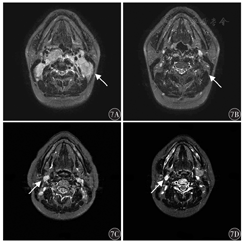

PSIP1和P4HB均高表达患者经过治疗前后临床影像学评估后,疗效都为有效,治疗后鼻咽淋巴结退缩明显(图7A、7B)。而PSIP1、P4HB均低表达鼻咽癌患者,淋巴结无显著改变(图7C、7D),提示PSIP1和P4HB基因高表达预示着更好的临床治疗效果。

注:箭头所指为转移淋巴结